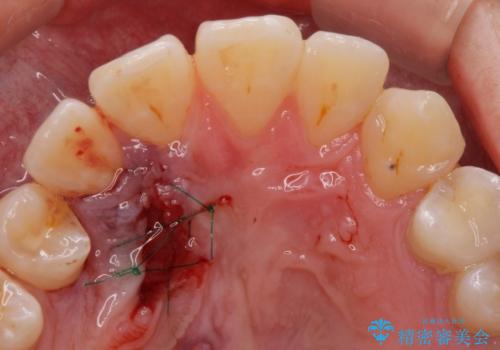

上顎の内側に歯が生えていて気になる。(静脈内鎮静下での抜歯)

担当医 青山卓弘